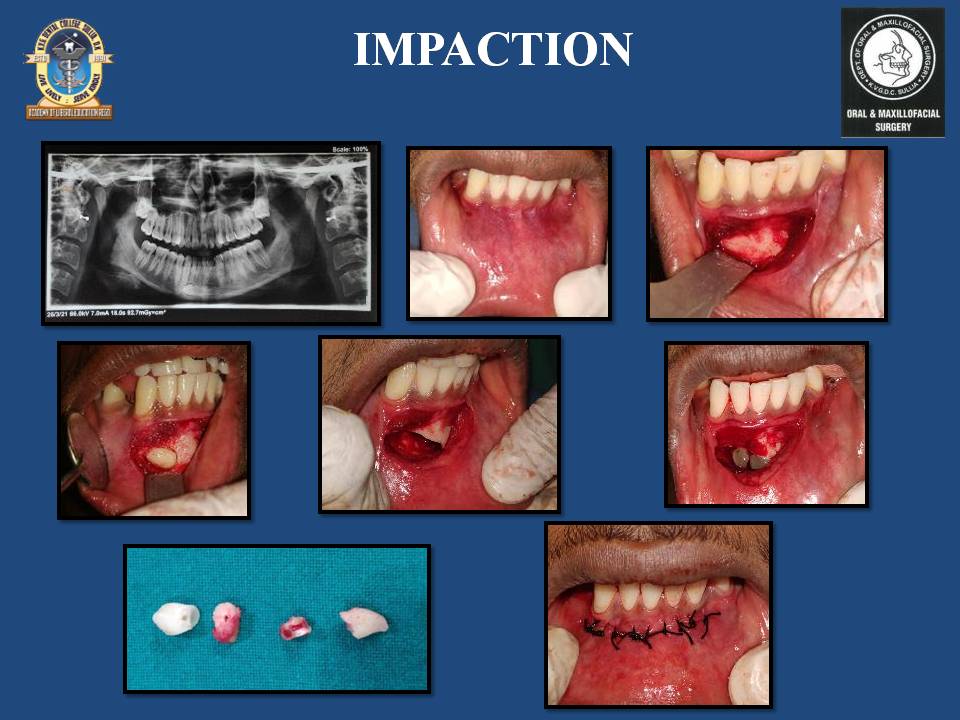

Oral and maxillofacial surgery is a branch of surgery to correct a wide spectrum of diseases, injuries and defects in the head, neck, face, jaws and the hard and soft tissues of the oral and maxillofacial region. It is a recognized international surgical speciality and it is one of the nine specialities of dentistry.

Surgical removal of multiple salivary stones